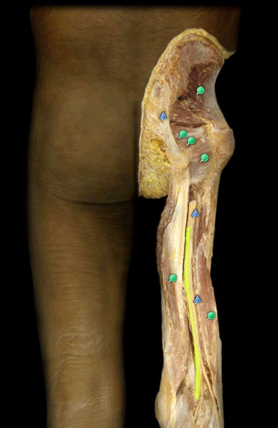

Iliotibial Tract

knowt flashcard image

Sciatic n.

L4-S3

largest nerve in body

Herniated intervertebral disks in lower lumbar region may produce symptoms